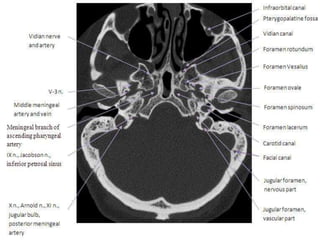

Anatomical Land marks.

• Pituatry area and cavernous sinus region.